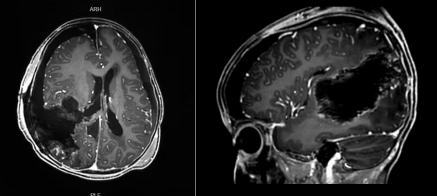

术前准备充分后,在麻醉科、PICU、输血科等多学科团队的紧密配合下,王超带领团队为轩轩施行了神经内镜下右侧额顶枕叶巨大占位切除术。经过3小时40分钟的紧张手术,困扰轩轩的巨大肿瘤被完整切除,手术取得圆满成功。

术后两周,轩轩恢复顺利,未出现任何神经功能损伤,精神状态也逐步好转。目前,轩轩已顺利衔接后续抗肿瘤治疗,实现了肿瘤全切与神经功能保留的理想治疗效果。